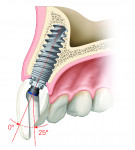

The implant industry is also developing new solutions to address these issues. One such innovative design is the angulated screw channel (ASC) abutment. This allows abutment angulation changes of up to 25 degrees, so screw-retained options can be readily used20 (Figure 9 and Figure 10).